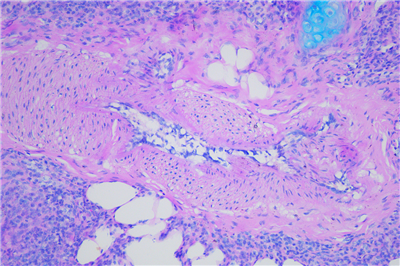

PAS染色步骤:

1脱蜡:65度30分钟,二甲苯脱蜡 5min×2次

2水化:将脱蜡后的切片经100%酒精,95%酒精,85%酒精,75%酒精,双蒸水各3min

3 入阿利新蓝染色液,染色15分钟。

4 蒸馏水洗3次,每次1-2分钟。

5 入过碘酸溶液,氧化5分钟

6入Schiff Reagent,浸染15分钟。

7 倾去Schiff Reagent,流水冲洗10分钟。

8(可选)入Leagene苏木素染色液,染核1-2分钟。

9用酸性分化液分化2-5秒,水洗。

10用Scott蓝化液反蓝,水洗3分钟。

11 逐级常规乙醇脱水。二甲苯透明,中性树胶封固。

12通过显微镜拍照,采集分析样本相关部位。